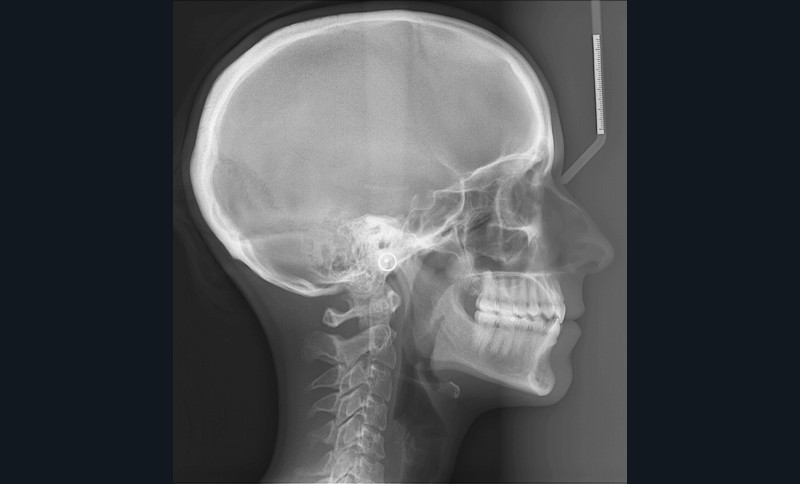

L’examen de la téléradiographie de profil fait apparaître un schéma squelettique normodivergent de classe I (fig. 8).